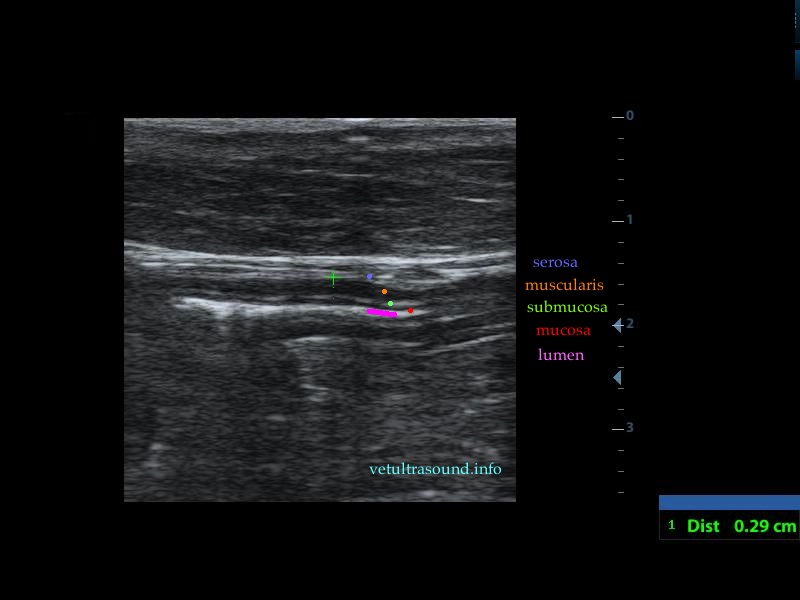

Findings: There was an increase in thickness of a segment of the small intestine, in which the normal layering was lost. This lesion extended for 3 cm(pic1). There was a restriction of the lumen, in this segment(pic2). In other parts of the ileum the muscularis propria was increased in thickness, compared to the thickness of the submucosa and the mucosa(pic3,4). The renal cortex of both kidneys was hyperechoic compared to the echogenesity of the liver and the spleen(pic5). A small amount of ascites was noted. The regional lymphnodes were enlarged and the mesenteric fat, which encircled the lesion of the small intestine, was hyperechoic.

Diagnose: These findings are compatible with alimentary tract lymphoma. There is a possibility that the kidneys are also infiltrated by lymphocytes.